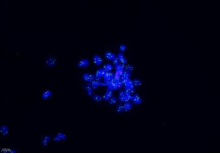

免疫熒光 |

| |